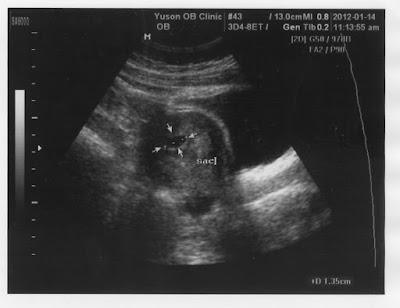

DSCF8249

寶寶的第一張照片.還看不到頭.1.35公分 (30天左右的)